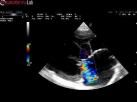

Our Specialty ServicesOur Specialty ServicesVeterinary Specialty ConsultationAbdominal UltrasoundEndoscopy Comprehensive Oncology Teleconsultation Echocardiogram Ultrasound-guided Fine Needle Aspiration Bone Marrow Aspiration/Biopsy Pericardiocentesis Arthrocentesis Cerebrospinal Fluid (CSF) Aspiration Balloon Dilation of Benign Esophageal Stricture